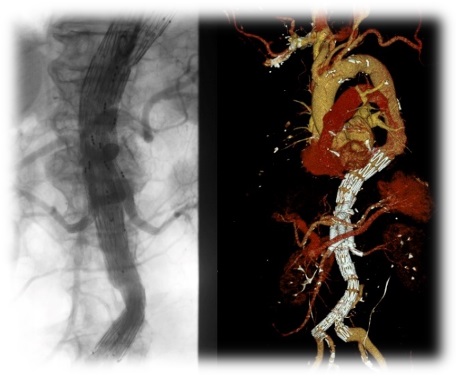

- Мастер-класс по применению браншированных стент-графтов при лечении аневризма торакоабдоминального отдела аорты

- Мастер-класс по применению фенестрированных стент-графтов при лечении юкстаренальных аневризм брюшной аорты

2024 год

- Международный мастер-класс по эндоваскулярному лечению аневризм торакоабдоминального отдела аорты с использованием методов интраоперационной фенестрации с участием экспертов из Китая

- Патент № 2786008 от 30.11.2021. «Способ гибридной реваскуляризации при многоуровневом поражении брахиоцефальных артерий». Авторы: Чернявский М.А., Чернов А.В., Соловьев В.А., Сусанин Н.В., Чернова Д.В., Одинцов Н.С., Белова Ю.К., Ванюркин А.Г.

- Патент № 2799059 от 03.07.2023. «Способ эндоваскулярной реваскуляризации хронических окклюзий периферических стентов в бедренно-подколенной позиции». Авторы: Чернявский М. А., Чернов А. В., Соловьев В.А., Сусанин Н. В., Чернова Д.В., Белова Ю.К., Ванюркин А.Г.

- Патент № 2835724 от 03.03.2025. «Способ эндопротезирования дуги аорты с направленной фенестрацией в устье левой подключичной артерии со сложной анатомией». Авторы: Чернявский М. А., Чернов А. В., Пантелеева Ю. К., Ванюркин А. Г., Чернова Д. В., Рзаев Э. Ф., Поплавский Е. О.